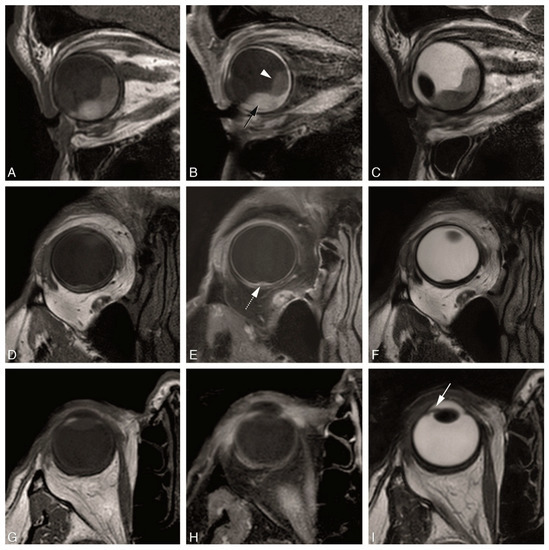

4.2. Anatomical MRI of Uveal Melanoma